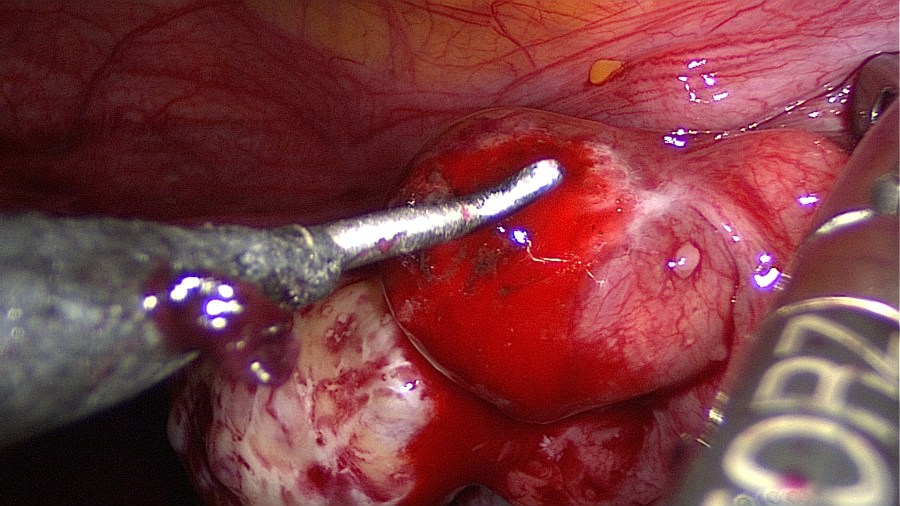

Grasp the contents with an atraumatic grasper and expell the tubal pregnancy en bloc. Failure to do so may increase risk of persistent ectopic tissue. Alternatively this may be performed with suction or aquadissection.

If need be, control the bleeding with tissue-sparing bipolar coagulation. In this case the tube (submerged in saline) does not require any coagulation or suturing.